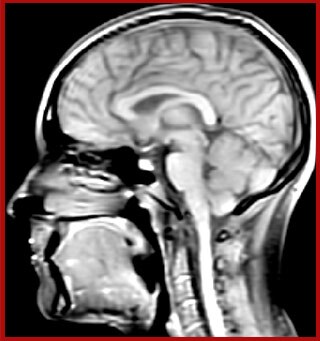

Sagittal 3D FLAIR with 0.3 mm3 voxel volume acquired in 5:12 min. using Compressed SENSE showing a (juxta)cortical MS lesion.